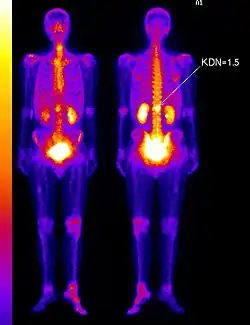

- коэффициент дифференциального накопления (КДН)

Исследования фармакокинетики золедроновой кислоты, меченной 99mTc, показало, что для её распределения характерна выраженная остеотропность на фоне высокой скорости выведения из органов, тканей и всего тела. Пик концентрации препарата в основных органах и тканях, включая почки, наблюдается через 10 минут после введения. В мочевом пузыре пик концентрации отмечается через 1 час после введения. Максимум накопления препарата в скелете (до 40 % введённой активности) наблюдается через 1 — 2 часа после введения. Высокое накопление препарата в скелете сохраняется до 8 — 12 часов наблюдения.

Особенности фармакокинетики золедроновой кислоты, меченной 99mTc, отличающейся быстрой скоростью выведения, на фоне высокой аффинности к участкам повышенного метаболизма и ускоренной резорбции в костной ткани, объясняют возможность проведения остеосцинтиграфии, уже через 1 час после введения, обеспечивая качественную визуализацию скелета.

Исследование начинается с внутривенного введения 99mTc-золедроновая кислота (Резоскан) с активностью 5 МБк/кг с последующим сканированием спустя 1-3 часа после инъекции, с обязательным предварительным опорожнением мочевого пузыря. Равномерное поглощение вещества костями обычно говорит о норме. Фокальное поглощение (локальное поглощение, отличающееся по интенсивности от такового в соседней кости) может свидетельствовать об аномалиях. Если фокальное поглощение интенсивнее, чем поглощение в соседней кости, это может быть признаком артрита, перелома или наличия метастазов. Менее интенсивное, чем в соседних костях, фокальное поглощение указывает на возможный некроз опухоли, лизис новообразования или последствия лучевой терапии. Размеры ни одной из коммерчески доступных гамма-камер не позволяют получить изображение всего тела взрослого человека без перемещения камеры или пациента. Таким образом, сканирование скелета проводится с помощью перемещения камеры вдоль длинной оси пациента или перемещения пациента вдоль камеры. Для сканирования скелета детекторы размещают в положениях 90° и 270°, пациент лежит на спине ногами по направлению к гентри. Затем стол вместе с пациентом перемещается в точку начала сканирования, в которой голова пациента находится в поле зрения камеры. Во время исследования пациент и стол перемещаются таким образом, что сканирование идёт с головы до ног. Получение изображений всего тела («whole body»), которые представляют собой относительные значения поглощения радиомаркера в области головы, груди, брюшной полости и ног, требует точного кодирования и сопоставления параметров сканирования и движения пациента. Большинство таких процедур проводится с помощью гамма-камер, содержащих по два детектора, так что передняя и задняя проекции снимаются одновременно.